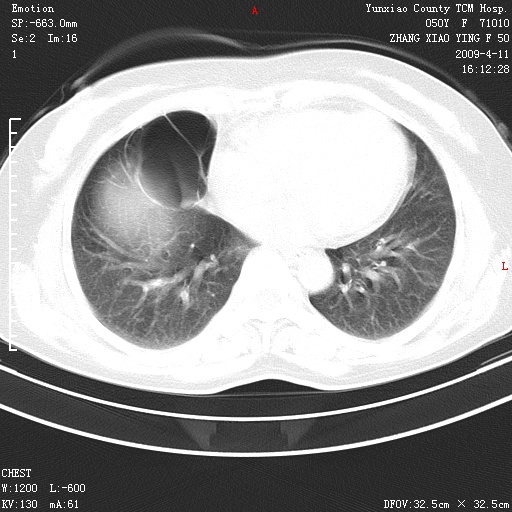

标题: CT19324:胸闷1周伴咳嗽 [打印本页]

标题: CT19324:胸闷1周伴咳嗽

肺囊肿并感染。

病灶周围肺纹受压移位走行较柔和,余肺里实质均匀,纹理如常,肺间质无显著纤维化,支持考虑孤立性肺囊肿

考虑右肺中叶肺囊肿。